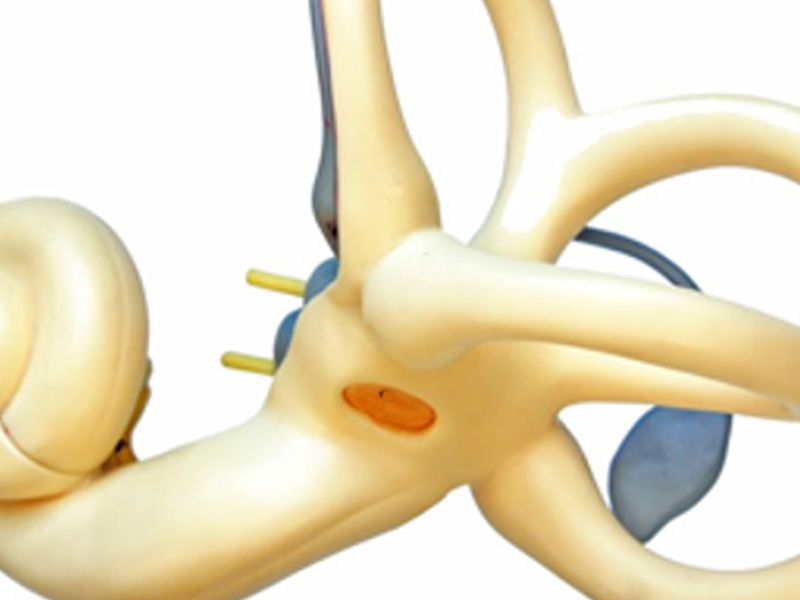

Avaliação do labirinto, órgão responsável pelo equilíbrio corporal.

Avaliação da estrutura do labirinto chamada sáculo e o ramo inferior do nervo vestibular.

Tratamento para indivíduos com Vertigem Posicional Paroxística Benigna (VPPB).